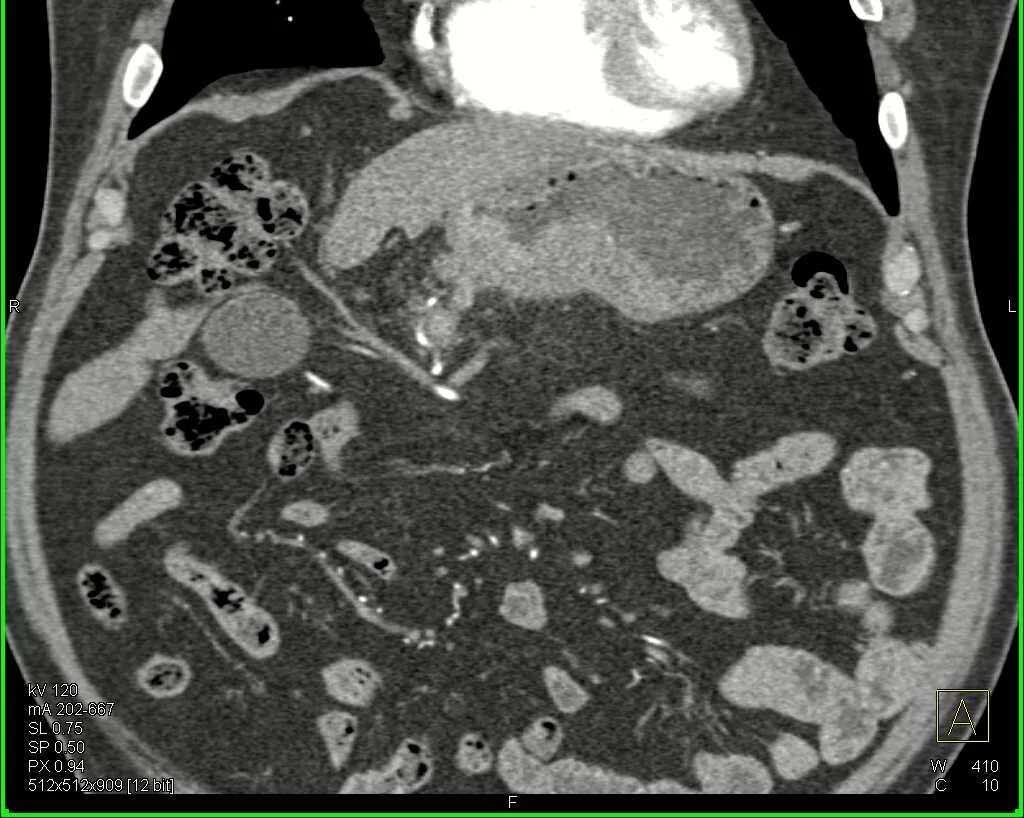

Язва желудка кт